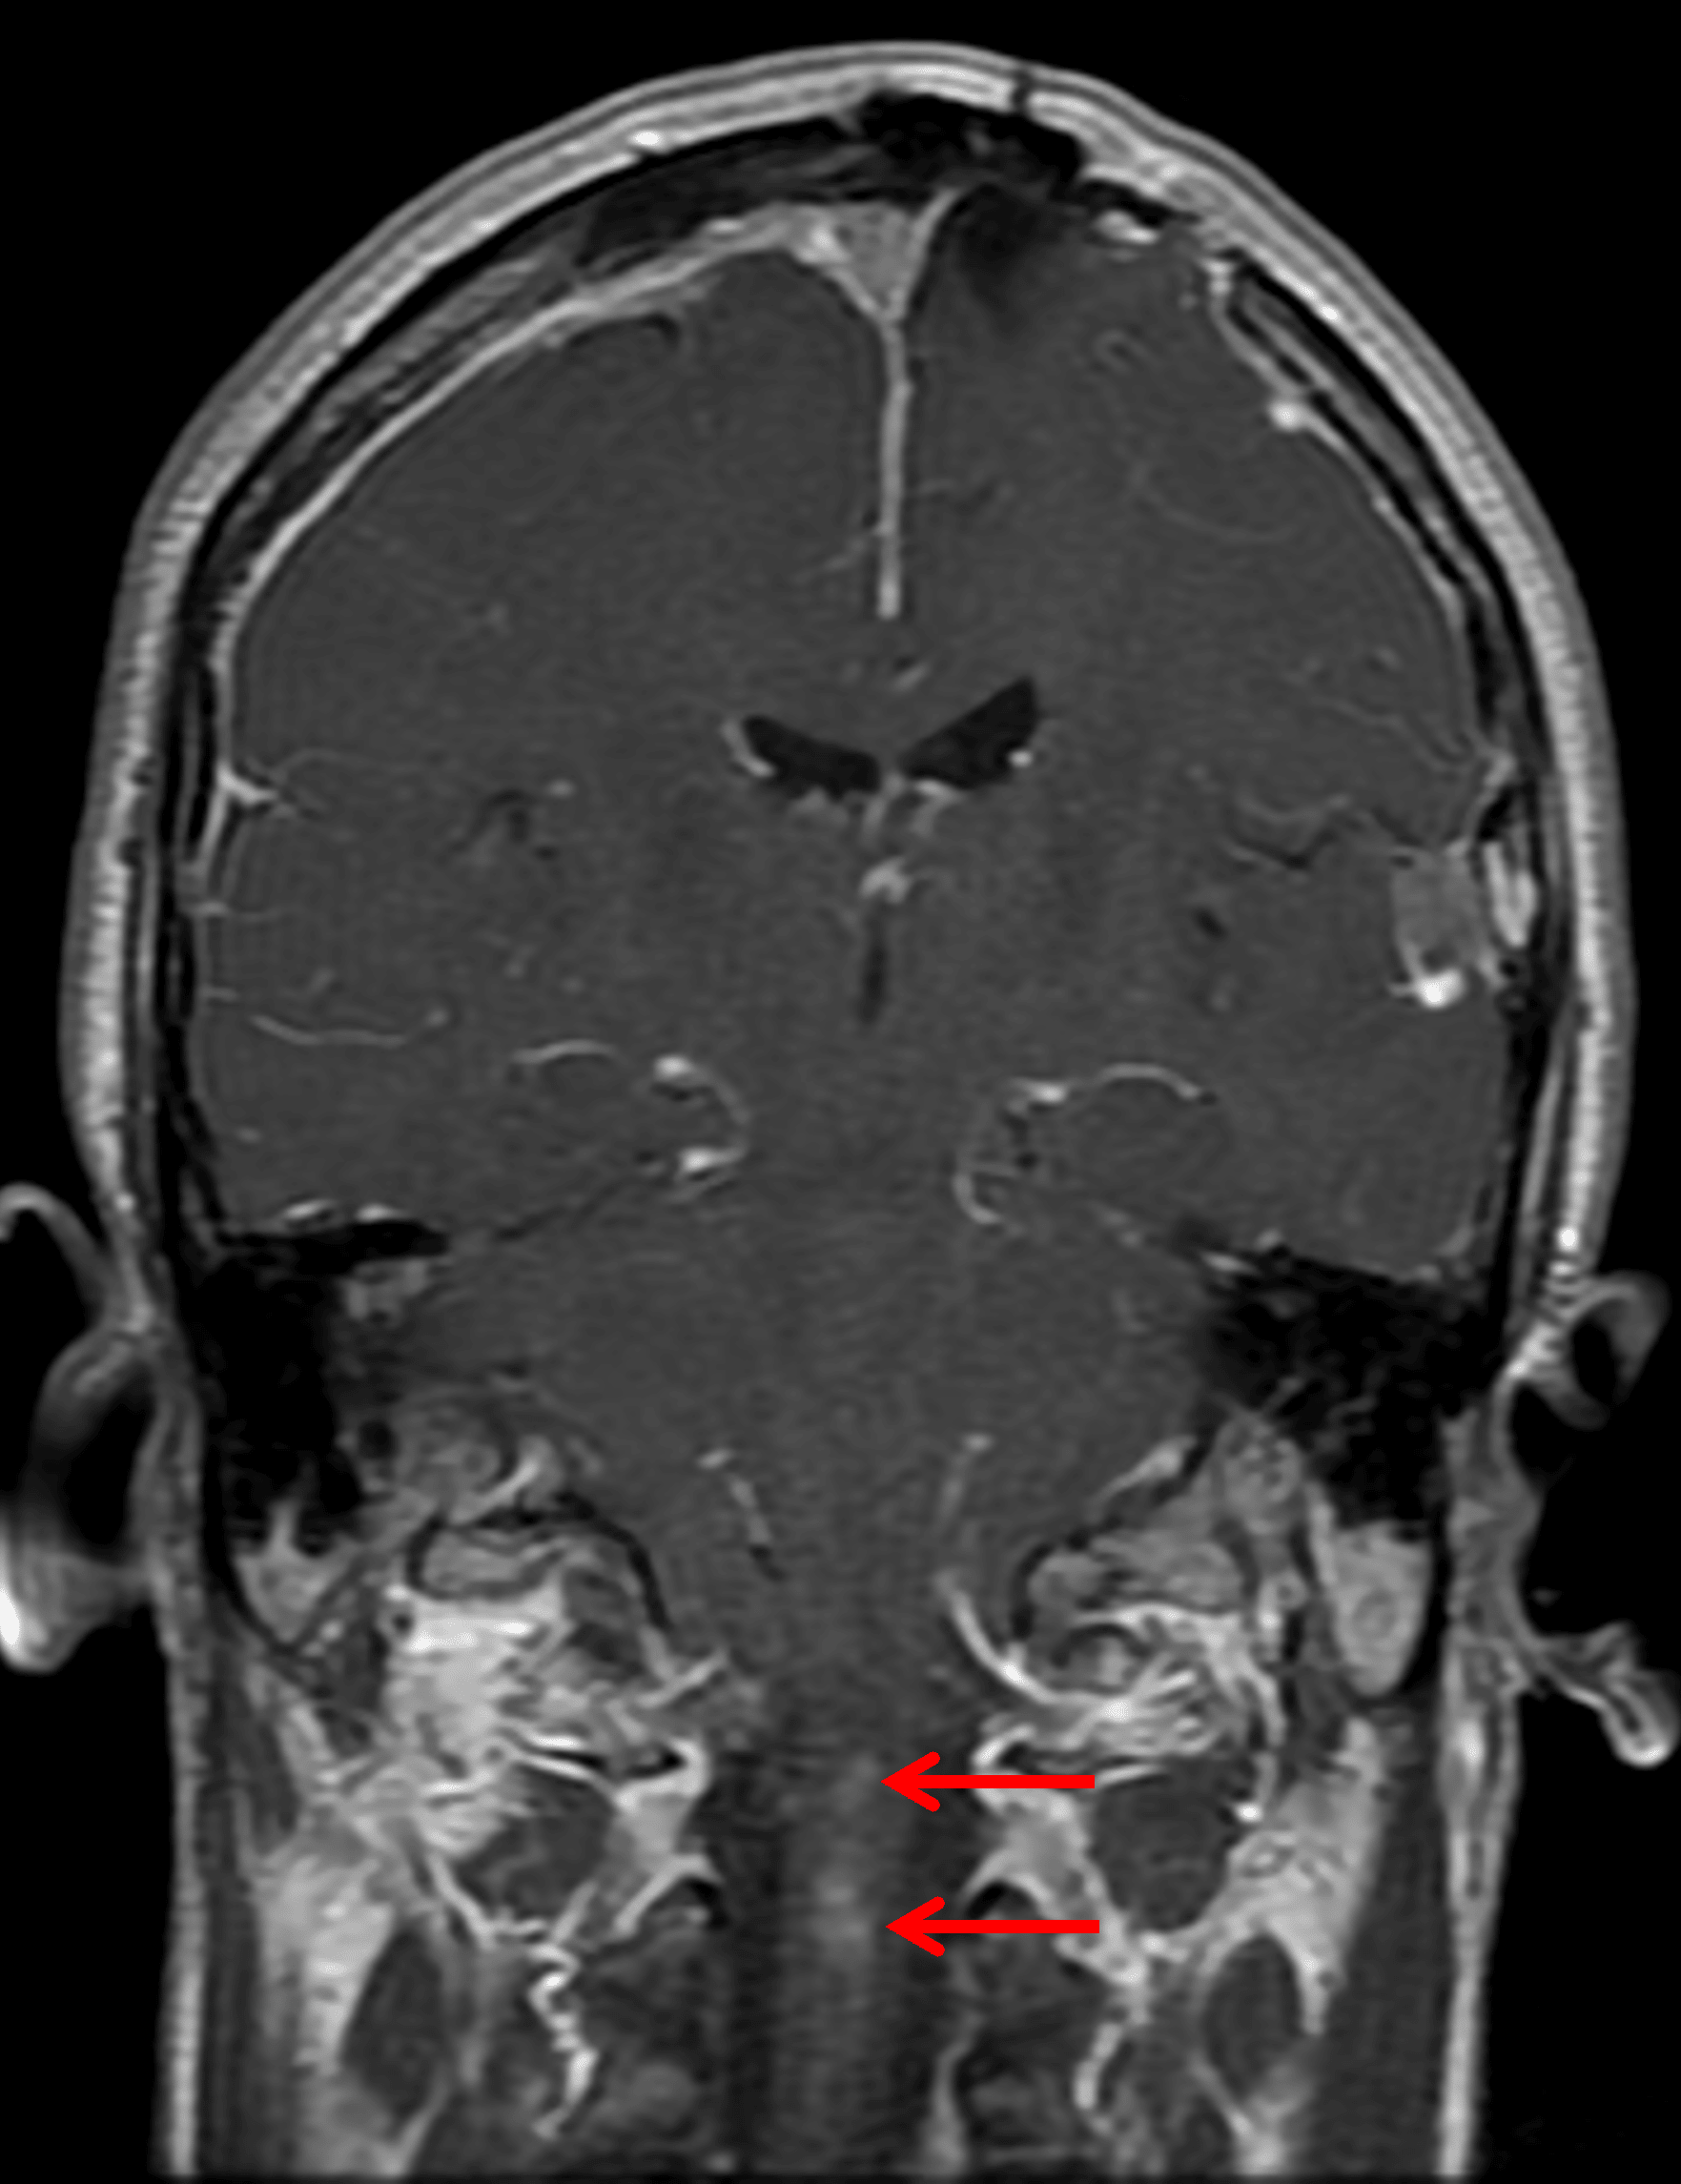

Enhancing intramedullary lesions in the upper cervical spinal cord (red arrows), likely representing ependymomas.

• Partially imaged enhancing lesions involving the upper cervical spinal cord